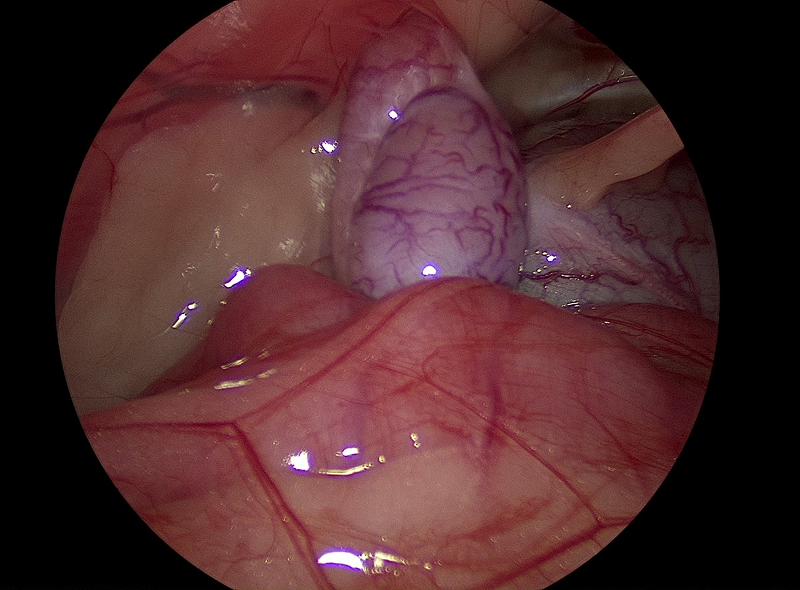

胆嚢粘液嚢腫と診断された犬の胆嚢

この後、腹腔鏡下胆嚢摘出術が実施された

腹腔鏡下胆嚢摘出術の様子